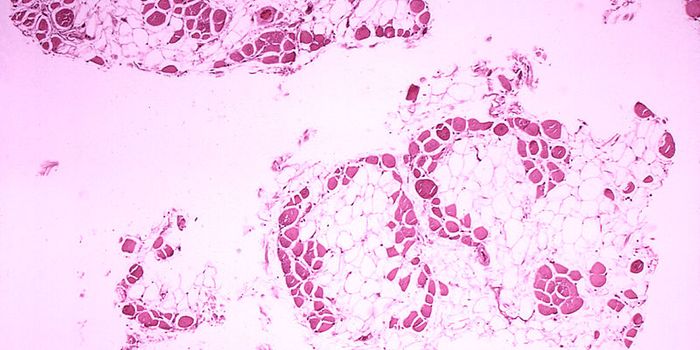

FEB 09, 2024CancerHistopathology describes the process of examining pieces of tissue using a microscope. Light microscopic (LM) exam ...